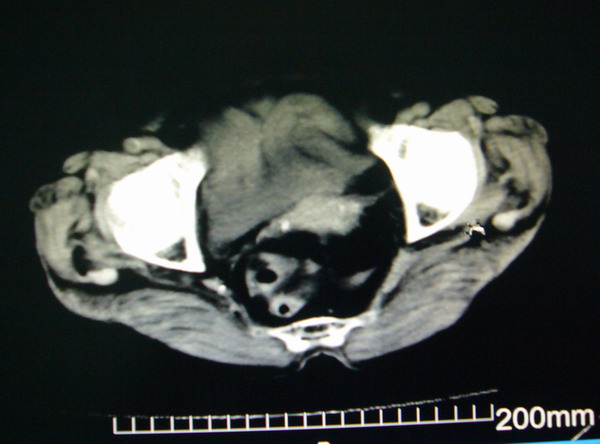

女:83y,转移性右下腹痛2小时,白细胞计数增高。

1.右侧肾盂扩大,肾盏无扩张,考虑:先天性肾盂变异可能性大。

2.胆囊扩张,考虑:胆囊炎。

3.阑尾区域可见以结节样高密度影,结合病史,考虑:阑尾结石,阑尾炎。

右下腹肠系膜增厚,结合病史支持阑尾炎.

右侧壶腹型肾盂可能,建议输路造影或增强

1.右侧肾盂扩大,考虑先天性肾盂变异或肾盂旁囊肿。

2.胆囊扩张,考虑胆囊炎。

3.阑尾区域可见结节样高密度影,结合病史考虑:阑尾结石、阑尾炎。